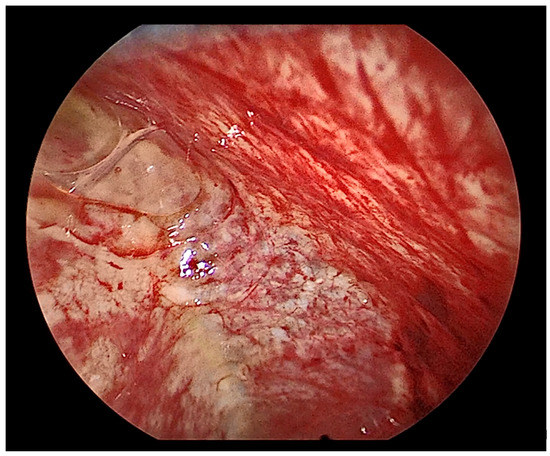

- Anevlavis, S.; Varga, C.; Nam, T.H.; Man, R.W.C.; Demetriou, A.; Jain, N.; Lanfranco, A.; Froudarakis, M.E. Is there any role for thoracoscopy in the diagnosis of benign pleural effusions. Clin. Respir. J. 2019, 13, 73–81. [Google Scholar] [CrossRef]

- Ellayeh, M.; Bedawi, E.; Banka, R.; Sundaralingam, A.; George, V.; Kanellakis, N.; Hallifax, R.; Abdelwahab, H.; Rezk, N.; Hewidy, A.; et al. Objective Thoracoscopic Criteria in Differentiation between Benign and Malignant Pleural Effusions. Respiration 2021, 101, 46–56. [Google Scholar] [CrossRef]